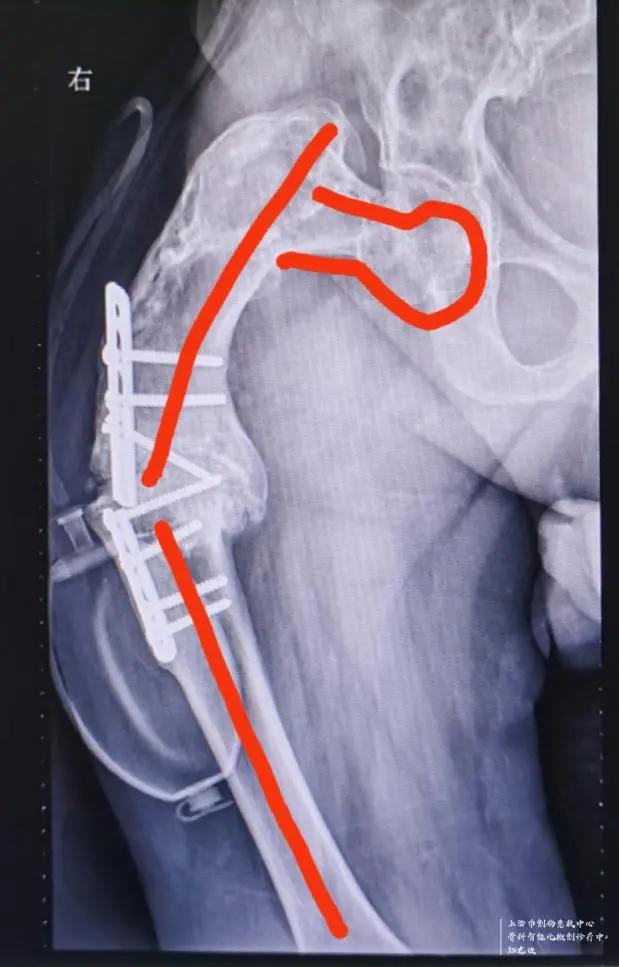

于1985年在某知名医院行右股骨干截骨矫形术,术后出现骨不连,截骨处假关节形成,内固定断裂,大腿畸形短缩进一步加重,左右腿粗细不一,长短相差近15公分,严重地影响了吴先生的正常生活、工作质量。吴先生曾经多次到知名大医院就诊,医生给出的建议是没有更好的治疗办法,也就宣判了吴先生右腿的终生残疾。此次摔倒雪上加霜的是,正好又摔断了畸形一侧大腿的股骨颈,新伤旧患叠加,让吴先生相当绝望!而让吴先生从绝望中起死回生的,是找到了十院骨科创伤中心主任郑龙坡教授------一个擅长啃骨科疑难杂症硬骨头的全国知名中青年专家。

经检查发现,如果是正常发育的大腿骨骼,可以根据骨折类型和患者的年龄不同,采取内固定或人工关节置换的方式进行手术。但由于吴先生右股骨近端骨纤维结构不良伴发严重畸形,且有断裂的内固定钢板存在,无法选择常规的治疗方式进行手术。

针对如此棘手的病例,且上海市血源非常紧张的情况下,郑龙坡教授团队经过充分的术前规划并与家属仔细沟通,决定分期对患者进行手术,一期对肱骨头骨折、肩关节脱位进行手术,二期采取肿瘤型假体置换的方式解决股骨颈骨折、股骨近端骨纤维结构不良伴严重畸形、股骨中段骨不连、内固定断裂等问题。

按照预定计划,患者一期进行了肩部的手术,手术及术后康复锻炼非常顺利。二期股骨手术,先把原来断裂的内固定物取出,再把畸形愈合的股骨近端从骨不连的地方切除,同时切除周围大量增生的骨痂,安装定制的人工股骨近端假体,并重建周围软组织平衡,历经2个小时的奋战,手术顺利完成。